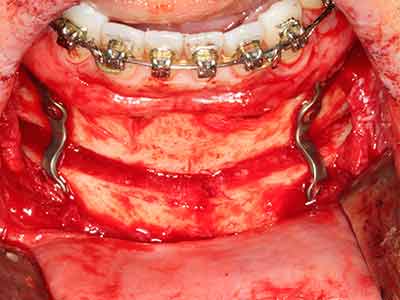

Пиезохирургията има допълнителни предимства при събиране на костни блокове. В допълнение към високата прецизност при остеотомията, описана по-горе, употребата на фините режещи накрайници значително намаляват загубата на материал. Голяма загуба на материал по време на събиране може да се очаква с дебелите накрайници, особено при употреба на борери Линдеман (Lakshmiganthan, Gokulanathan et al. 2012). Базалното разделяне, което е необходимо, особено за присадка на блок при ретромолар, е улеснено от специално създадени правоъгълни триони. В резултат на това, пиезохирургията е разглеждана като прецизна, улеснена и безопасна процедура за събиране на костни блокове в ретромоларното пространство (Happe 2007) (Фиг. 1-12).

Костната тъкан е не само минерализирана структура, тя съдържа и съществено количество колагенови влакна. Това означава, че тя има не само добра компресивна сила, но и известна степен на гъвкавост, която може да се възприеме като предимство при извършване на костна аугментация. В класическата процедура по разширяване чрез костно разделяне, атрофиралият алвеоларен гребен е разделен надлъжно и внимателно разширен след достигане на подходящата остеотомна дълбочина (Фиг. 13-16), в идеалния случай без допълнително отстраняване на периостеума (Brugnami, Caiazzo et al. 2014, Stricker, Fleiner et al. 2014). Системите с винт и пластини с увеличаване на разстоянието при разширяване са доказали ефективността си при разделяне на двете костни ламели, оставайки под прага на фрактурите. В общи линии, оставащата ширина на костта от поне 3–4 mm е задължителна (Chiapasco, Zaniboni et al. 2006), за да се гарантира добра гъвкавост и достатъчно костно покритие за бъдещото поставяне на импланти. Ако е необходимо, вертикалната остеотомия на едната или двете страни може да подобри гъвкавостта. Комбинацията с допълнителни техники за аугментация, особено в букалната страна, е описана като алтернатива на класическата техника.

Процедурата по разделяне е атравматична и няма голяма загуба на пространство, използвайки пиезотриони, и няма значителна разлика между импланти в разделени челюсти и импланти в алвеоларния гребен без костен дефицит (Chiapasco, Zaniboni et al. 2006, Danza, Guidi et al. 2009). Въпреки това, важно е да има достатъчно и продължително охлаждане, особено при ограничено и дълбоко разделяне, за да се избегне термичен стрес в апикално-остеотомните зони.